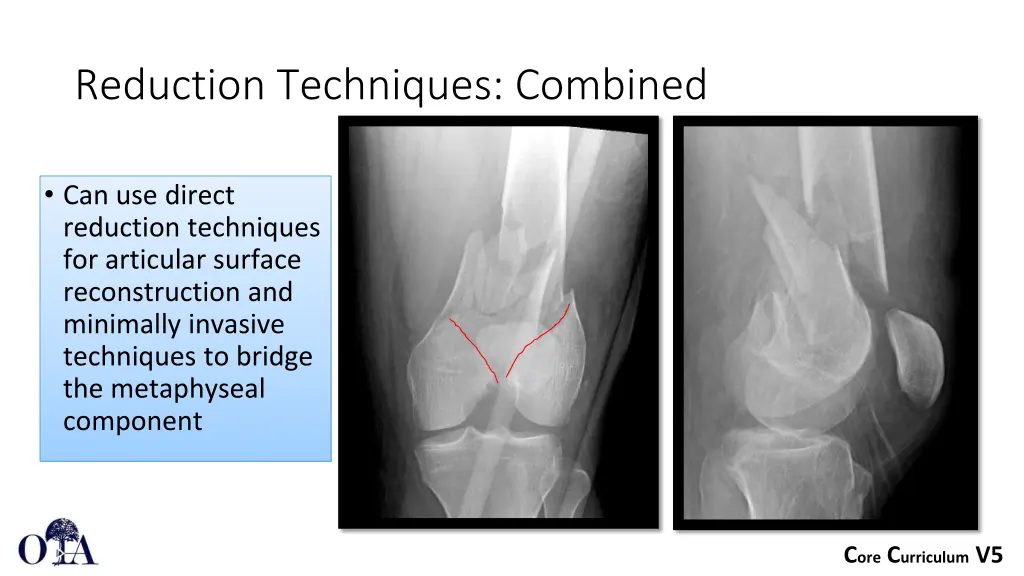

Reduction Techniques: Combined Can use direct reduction techniques for articular surface reconstruction and minimally invasive techniques to bridge the metaphyseal component Core Curriculum V5

Direct reduction of articular surface Lateral parapatellar arthrotomy to visualize articular reduction Direct reduction utilizing shanz pins to control fracture fragments, colinear clamp to compress articular surface Core Curriculum V5

Proximal screws inserted percutaneously Bridge plating of metaphyseal component Core Curriculum V5